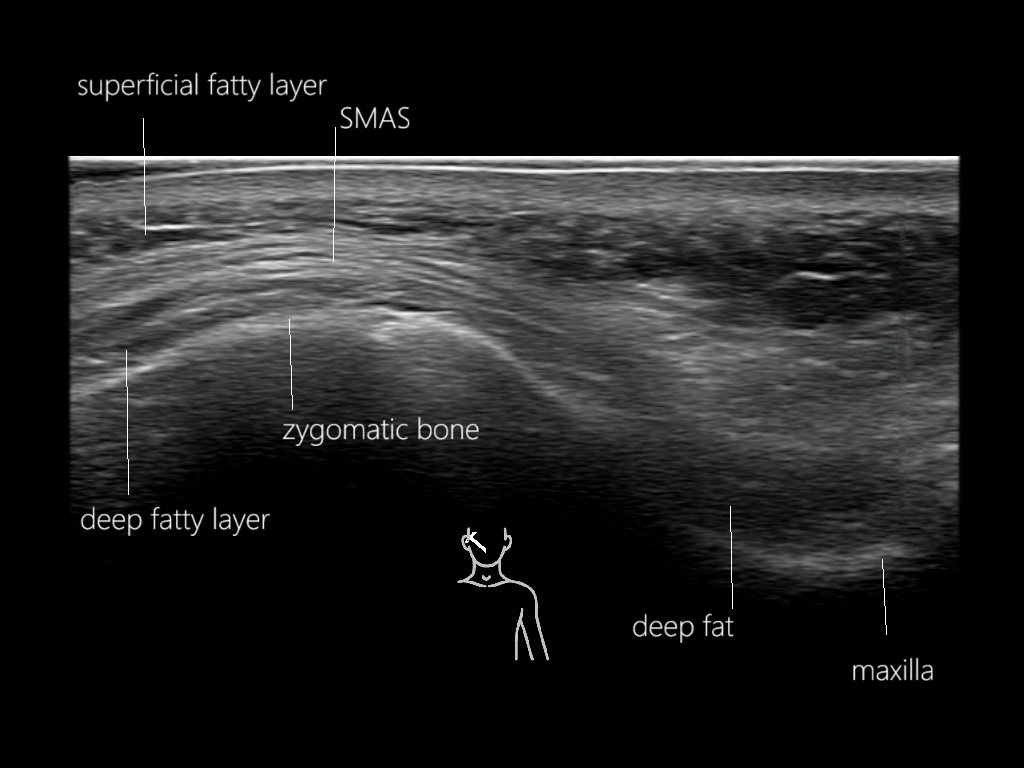

Study the first image to recognize the different layers. If you are sure about the layers, swipe to the second image to view the answer (if applicable).